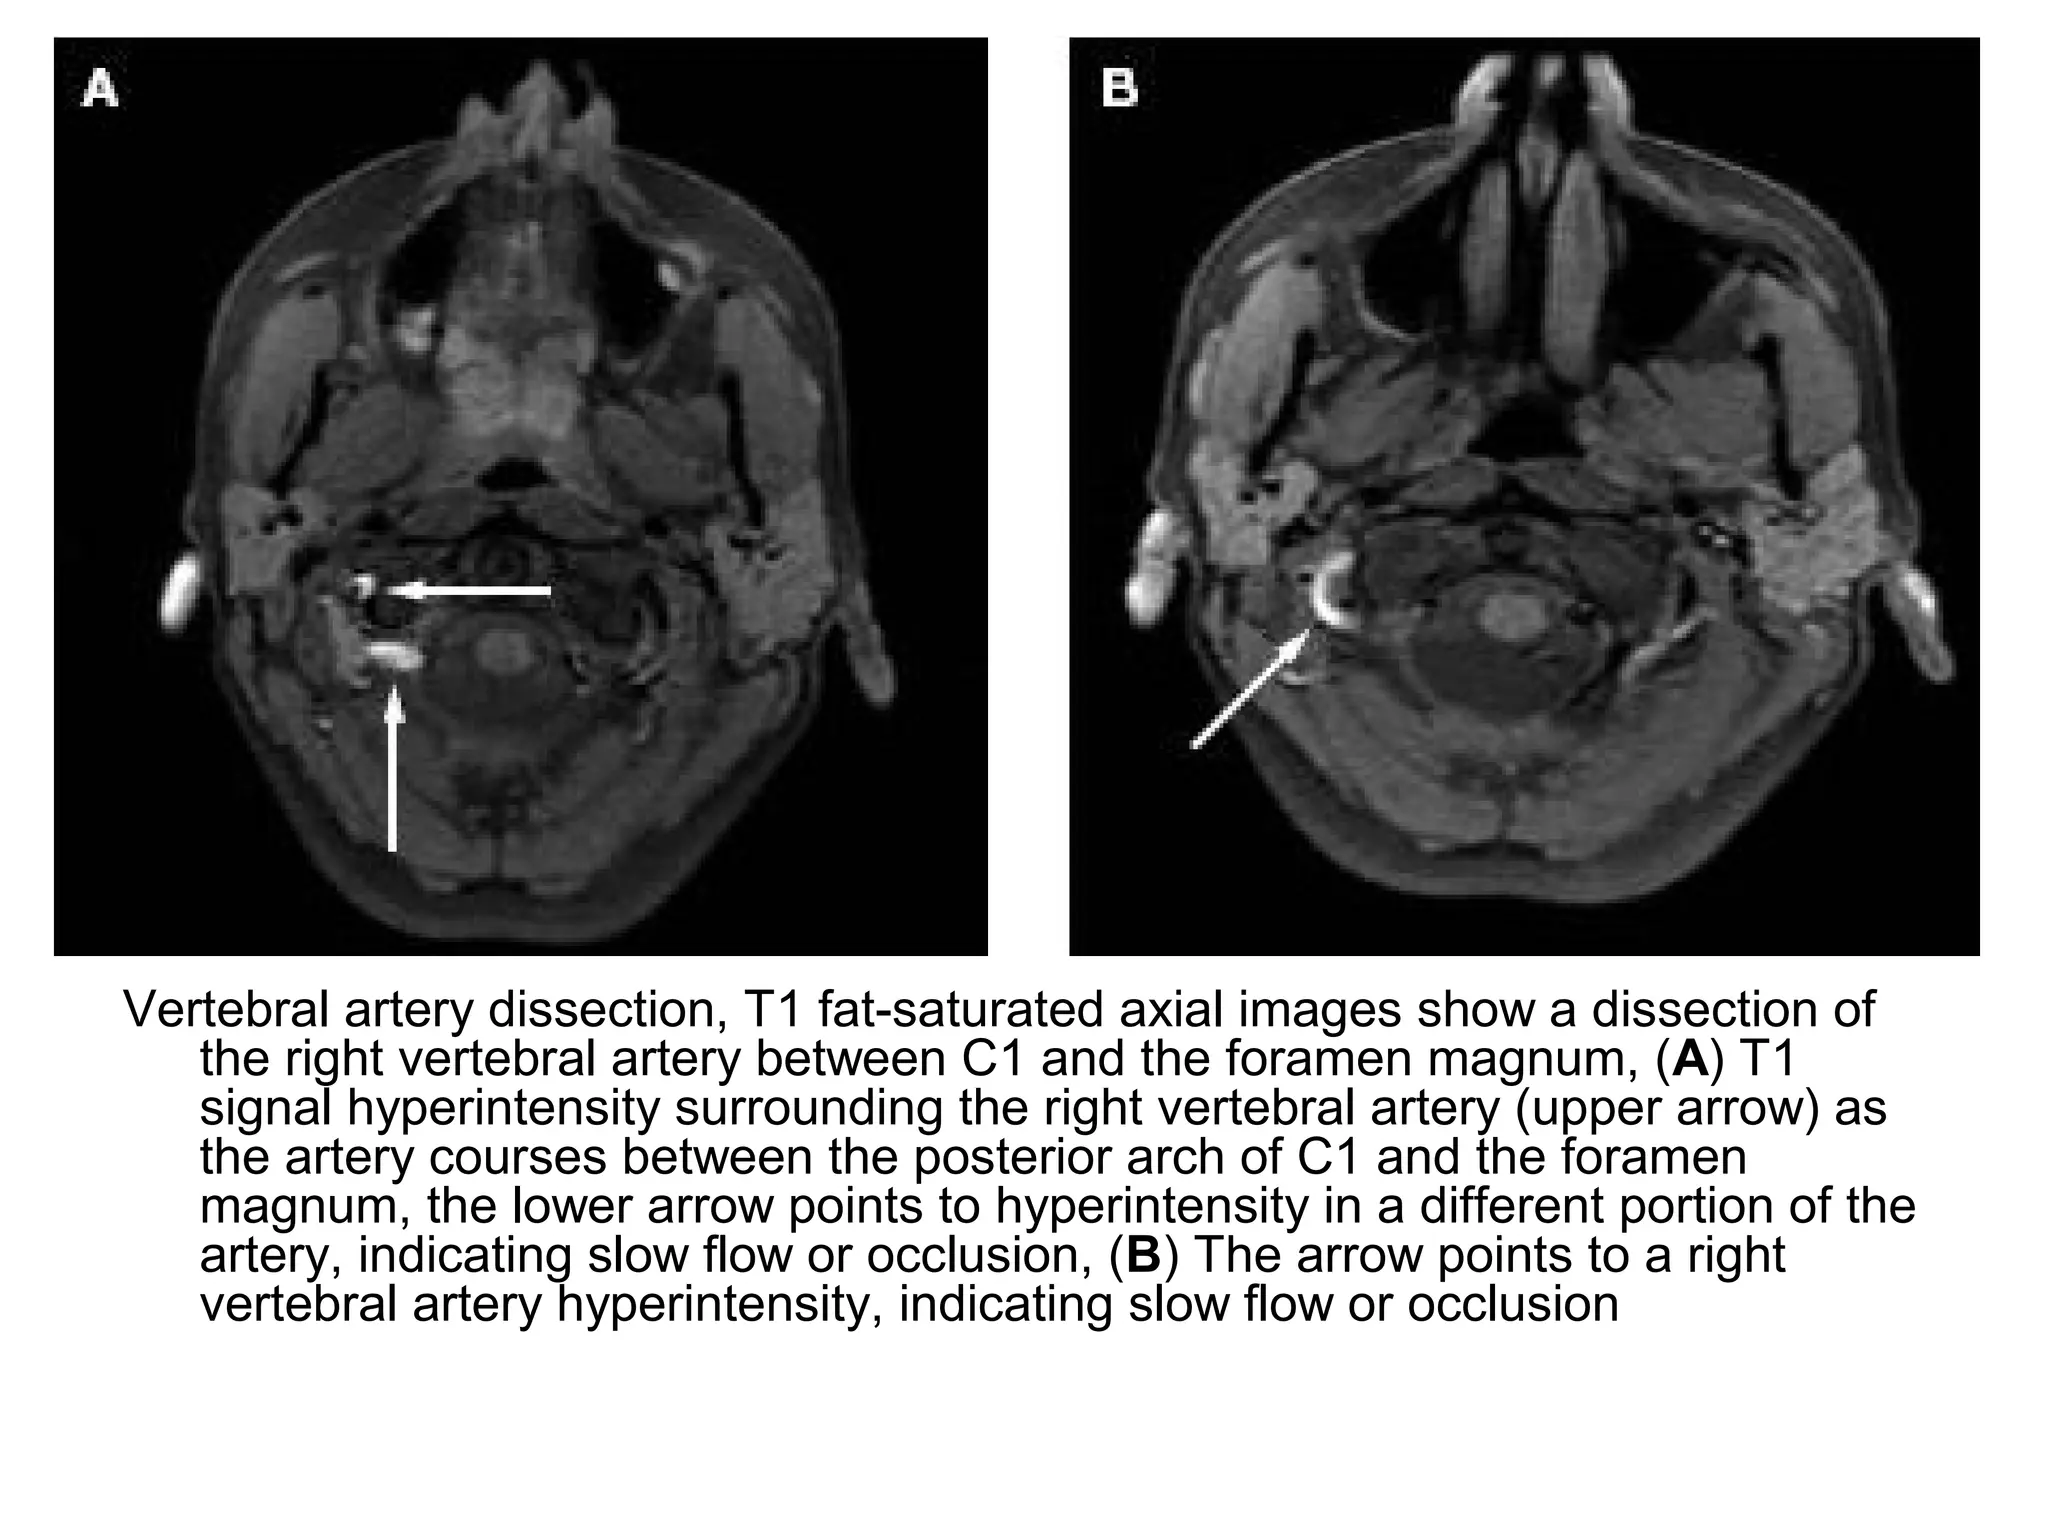

Vertebral artery dissection, T1 fat-saturated axial images show a dissection of

the right vertebral artery between C1 and the foramen magnum, (A) T1

signal hyperintensity surrounding the right vertebral artery (upper arrow) as

the artery courses between the posterior arch of C1 and the foramen

magnum, the lower arrow points to hyperintensity in a different portion of the

artery, indicating slow flow or occlusion, (B) The arrow points to a right

vertebral artery hyperintensity, indicating slow flow or occlusion

Vertebral artery dissection,T1 fat-saturated axial images show a dissection of the right vertebral artery between C1 and the foramen magnum, (A) T1 signal hyperintensity surrounding the right vertebral artery (upper arrow) as the artery courses between the posterior arch of C1 and the foramen magnum, the lower arrow points to hyperintensity in a different portion of the artery, indicating slow flow or occlusion, (B) The arrow points to a right vertebral artery hyperintensity, indicating slow flow or occlusion